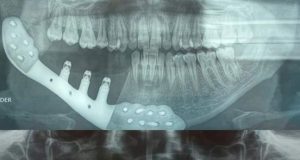

HOSPITAL NACIONAL DOS DE MAYO REALIZA PRIMER IMPLANTE DE TITANIO EN...

El Ministerio de Salud (Minsa) informa que el equipo médico del servicio de cabeza y cuello, y maxilofacial del Hospital Nacional Dos de Mayo...